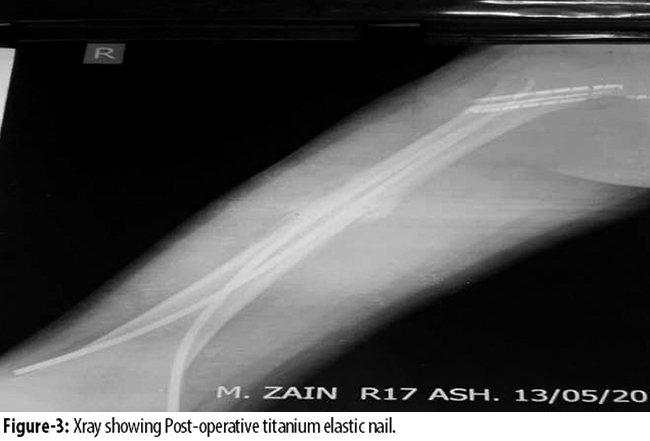

The diameter of the individual nail was selected as per Flynn\\\'s formula (diameter of nail = width of the narrowest point of the medullary canal on anteroposterior [AP] and Lateral view × 0.4mm) and on intraoperative assessment. The diameter of the nail was chosen so that each nail occupied at least 30% to 40% of the medullary cavity. Fractures were reduced using fluoroscopic guidance. Nails were inserted in retrograde fashion. In retrograde elastic nailing medial and lateral incisions were made 2.5-3.5cm proximal to distal physis (Figure-3).

The nails were pre-bent sufficiently so that apex of the bowed nails rested at the same level on the fracture site to ensure a good equal recoil force. The nails were driven proximally in divergent manner and the tips got anchored approximately 1cm proximal to the physis. Postoperatively, patients were nursed in supine position with the operated leg elevated on a pillow. Patients were mobilised without weight-bearing on the 5th to 7th day postoperatively. Partial weight-bearing was started at three weeks and full weight-bearing by 6 to 8 weeks.